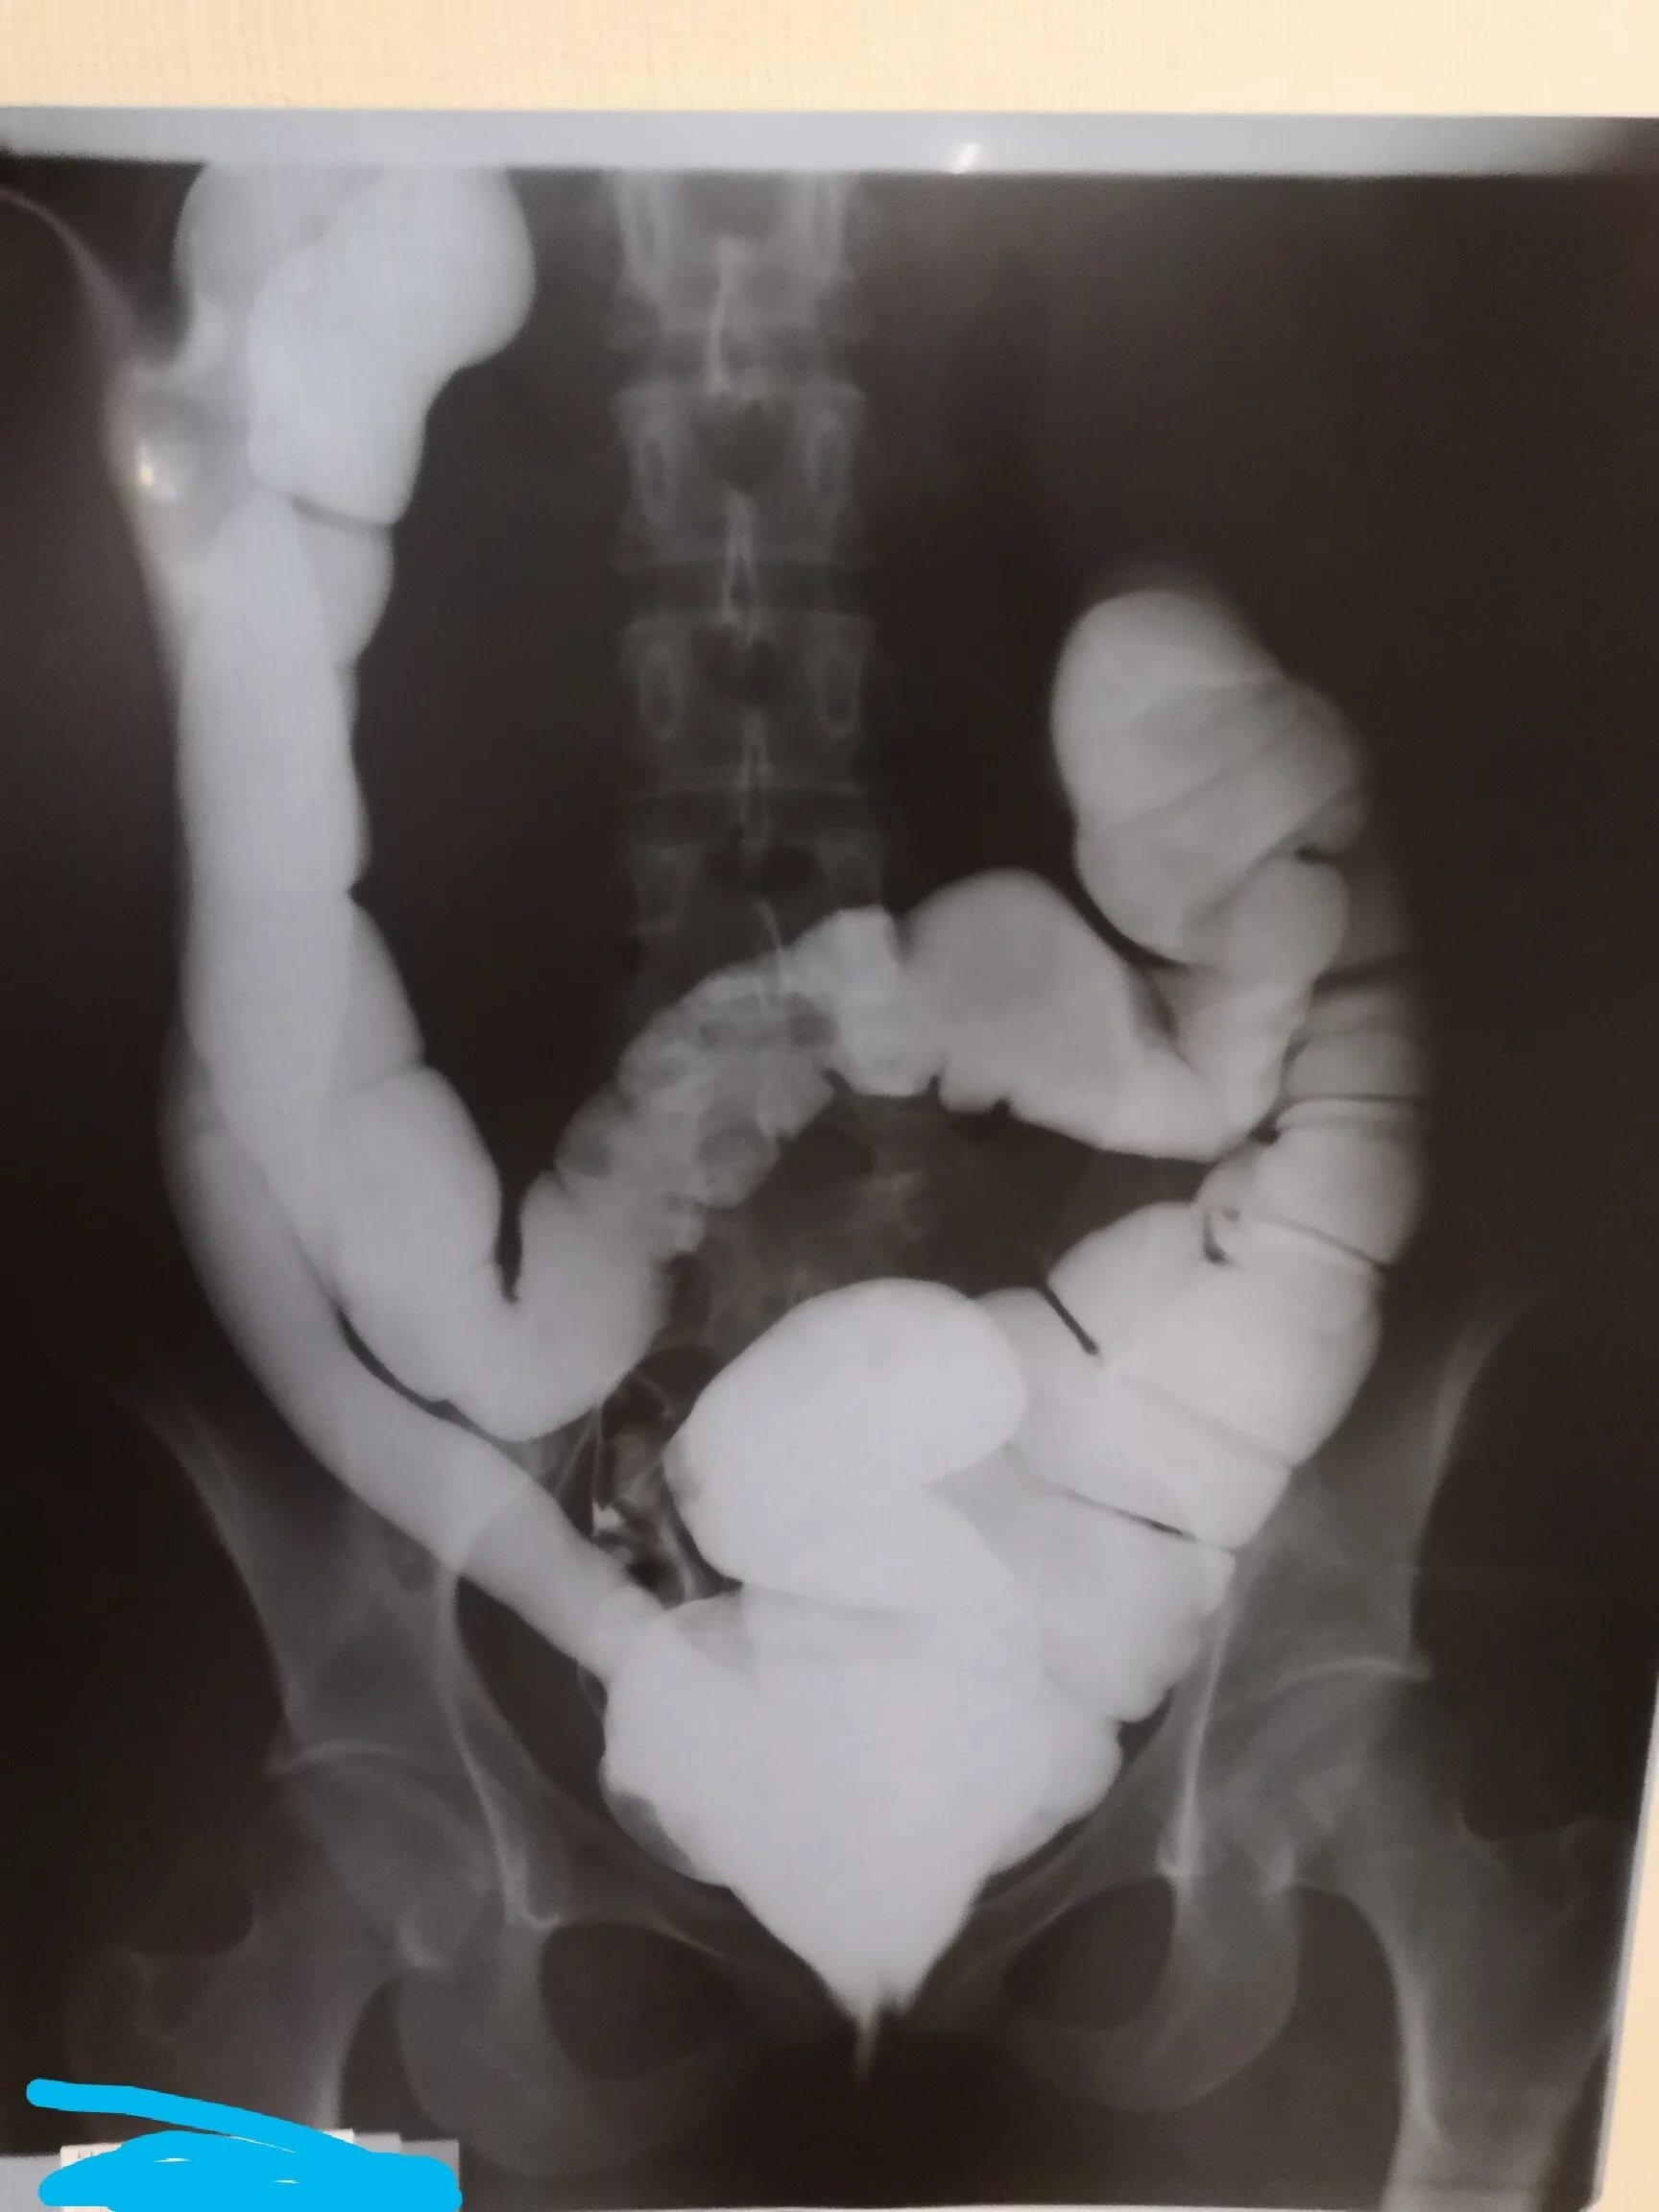

Долихоколон симптомы у взрослых